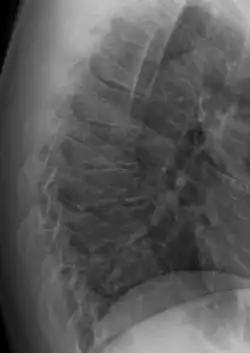

Scheuermann's disease

| Scheuermann's disease on lateral Xray of the T spine | |

Scheuermann's disease is a skeletal disorder.[3] It describes a condition where the vertebrae grow unevenly with respect to the sagittal plane; that is, the posterior angle is often greater than the anterior. This uneven growth results in the signature "wedging" shape of the vertebrae, causing kyphosis. It is named after Danish surgeon Holger Scheuermann.[4][5][6]

In addition to the pain associated with Scheuermann's disease, many individuals with the disorder have loss of vertebral height, and depending on where the apex of the curve is, may have a visual 'hunchback' or 'roundback'. It has been reported that curves in the lower thoracic region cause more pain, whereas curves in the upper region present a more visual deformity. Nevertheless, it is typically pain or cosmetic reasons that prompt sufferers to seek help for their condition. In studies, kyphosis is better characterized for the thoracic spine than for the lumbar spine.[7][8]

The seventh and tenth thoracic vertebrae are most commonly affected. It causes backache and spinal curvature. In very serious cases it may cause internal problems and spinal cord damage. The curvature of the back decreases height, thus putting pressure on internal organs, wearing them out more quickly than the natural aging process; surgical procedures are almost always recommended in this case.

Diagnosis is typically by medical imaging. The degree of kyphosis can be measured by Cobb's angle and sagittal balance.